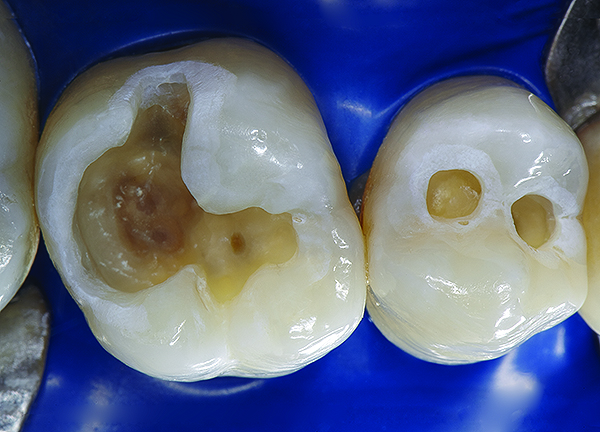

The mechanism of adhesion is similar for enamel and dentin—a micromechanical entanglement of monomers into the enamel microporosities or collagen interfibrillar spaces created by acid dissolution of mineralized tissues.45,46 When evaluating restorative success, the marginal integrity achieved by this procedure becomes a priority since an intact restorative–tooth interface is essential to the exclusion of bacteria and the interfacial hydrodynamic equilibrium of the dentino-pulpal complex (Figure 8 through Figure 11).

Figure 8. AND Figure 9. After the preparations were cleaned with 2% chlorhexidine, a selective etching of the cavosurface enamel was performed with 37.5% phosphoric acid gel for 10 seconds, rinsed for 5 seconds, and gently air dried. Notice the selective etch pattern of the enamel demonstrating a frosty appearance.

Figure 8

Figure 9